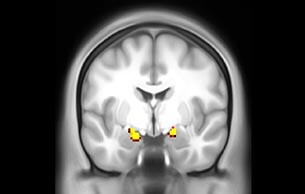

BOLD fMRI activation, depicted in color, of left anterior insula (MNI plane z = 8 mm) in a single subject by a contrast between viewing and matching faces with negative emotion (angry, sad, scared) versus happy faces. The voxelwise threshold is p < 0.001, and colored voxels survive false discovery rate correction to p < 0.05. The activated voxels in color are overlaid on the subject's own 3D-TFE image displayed in grayscale, after transforming the data to MNI space. The fMRI pulse sequence was a single shot FFE echo planar acquisition using MultiBand SENSE factor 6, dS SENSE factor 1, isotropic voxel size 2.4 mm, 60 transverse slices, TR 950 ms, TE 30 ms, flip angle 52 degrees, 517 dynamic scans, total scan duration 8:21 minutes. Image provided by James M. Bjork, PhD, Associate Professor of Psychiatry at VCU.

Emotional n-back task combines a test of working memory with the use of emotive (faces) and neutral (places) images. The contrast in the images is between the activity when faces are presented compared to places, showing activation in the amygdala, fusiform, and occipital face areas.

Group analysis of 88 9- and 10-year olds part of ABCD, all scanned at UVM on Philips Achieva 3.0T dStream. Scale runs from red p=0.001 to yellow p<10ˆ-5. Images provided by Dr. Watts.

Acquisition using the ABCD protocol for fMRI with TR 800 ms, TE 30 ms, flip angle 52°, 2.4 mm isotropic imaging resolution with a 216×216×144 mm3 field of view using a MultiBand acceleration factor of 6 (60 slices, no gap). Two runs of 5 minutes per subject.